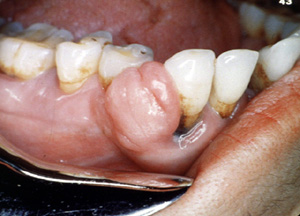

Éste es un ejemplo bastante típico de una lesión  nodular, firme cubierta por  epitelio normal. El color indica que hay proliferación vascular.

Este ejemplo típico se ulcera focalmente pero es asintomático. Este varón de 48 años de edad declaró que la lesión se había estado agrandando durante 5 años. Los dientes aparecen separados. Es frecuente  que estas lesiones pueden ser bastante agresivas y pueden cambiar de sitio a los dientes.